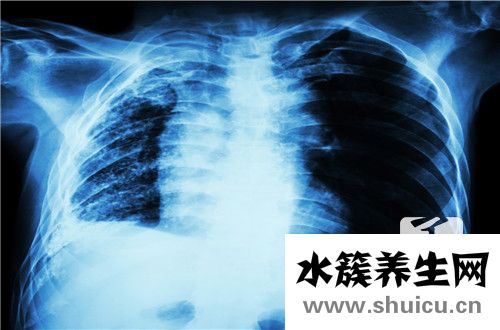

結核性腹膜炎是一種非常常見的腹部疾病,在女性中最常見。 主要癥狀通常是全身腹脹,腹痛,發燒和汗水,很容易失去能量,缺乏能量和精力。 這種疾病是由結核病引起的。 在由感染引起的腹部,治療應徹底立即,...